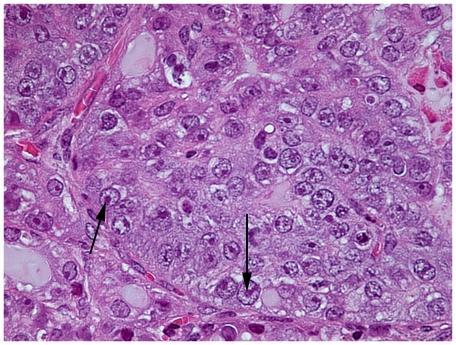

Lo-MYC and Hi-MYC mice develop prostatic intraepithelial neoplasia (PIN) and prostatic adenocarcinoma as a result of MYC overexpression in the mouse prostate. However, prior studies have not determined precisely when, and in which cell types, MYC is induced. Using immunohistochemistry (IHC) to localize MYC expression in Lo-MYC transgenic mice, we show that morphological and molecular alterations characteristic of high grade PIN arise in luminal epithelial cells as soon as MYC overexpression is detected. These changes include increased nuclear and nucleolar size and large scale chromatin remodeling. Mouse PIN cells retained a columnar architecture and abundant cytoplasm and appeared as either a single layer of neoplastic cells or as pseudo-stratified/multilayered structures with open glandular lumina-features highly analogous to human high grade PIN. Also using IHC, we show that the onset of MYC overexpression and PIN development coincided precisely with decreased expression of the homeodomain transcription factor and tumor suppressor, Nkx3.1. Virtually all normal appearing prostate luminal cells expressed high levels of Nkx3.1, but all cells expressing MYC in PIN lesions showed marked reductions in Nkx3.1, implicating MYC as a key factor that represses Nkx3.1 in PIN lesions. To determine the effects of less pronounced overexpression of MYC we generated a new line of mice expressing MYC in the prostate under the transcriptional control of the mouse Nkx3.1 control region. These "Super-Lo-MYC" mice also developed PIN, albeit a less aggressive form. We also identified a histologically defined intermediate step in the progression of mouse PIN into invasive adenocarcinoma. These lesions are characterized by a loss of cell polarity, multi-layering, and cribriform formation, and by a "paradoxical" increase in Nkx3.1 protein. Similar histopathological changes occurred in Hi-MYC mice, albeit with accelerated kinetics. Our results using IHC provide novel insights that support the contention that MYC overexpression is sufficient to transform prostate luminal epithelial cells into PIN cells in vivo. We also identified a novel histopathologically identifiable intermediate step prior to invasion that should facilitate studies of molecular pathway alterations occurring during early progression of prostatic adenocarcinomas.

Lo-MYC 和 Hi-MYC 小鼠由于 MYC 在小鼠前列腺中的过度表达而发展为前列腺上皮内瘤形成(PIN)和前列腺腺癌。然而,先前的研究并未确定 MYC 何时以及在何种细胞类型中被诱导。通过免疫组织化学(IHC)定位 Lo-MYC 转基因小鼠中的 MYC 表达,我们表明,一旦检测到 MYC 过度表达,具有高级别 PIN 特征的形态和分子改变就会出现在腔上皮细胞中。这些变化包括核和核仁大小增加以及大规模染色质重塑。小鼠 PIN 细胞保留柱状结构和丰富的细胞质,表现为单层或假分层/多层结构,具有开放的腺体腔-高度类似于人类高级别 PIN 的特征。同样通过 IHC,我们表明 MYC 过度表达和 PIN 发育的开始与同源域转录因子和肿瘤抑制因子 Nkx3.1 的表达下调精确吻合。实际上,所有正常的前列腺腔上皮细胞都表达高水平的 Nkx3.1,但在 PIN 病变中表达 MYC 的所有细胞都表现出 Nkx3.1 的明显减少,这表明 MYC 是一种关键因素,可在 PIN 病变中抑制 Nkx3.1 的表达。为了确定 MYC 表达程度较低的影响,我们生成了一条在前列腺中表达 MYC 的新小鼠系,其表达受小鼠 Nkx3.1 控制区的转录控制。这些“超级 Lo-MYC”小鼠也发展为 PIN,尽管形式不太激进。我们还确定了从小鼠 PIN 进展为浸润性腺癌的一个在组织学上定义的中间步骤。这些病变的特征是失去细胞极性、多层化和筛状形成,以及 Nkx3.1 蛋白的“反常”增加。Hi-MYC 小鼠中也发生了类似的组织病理学变化,尽管动力学加快。我们使用 IHC 的结果提供了新的见解,支持 MYC 过度表达足以将前列腺腔上皮细胞在体内转化为 PIN 细胞的观点。我们还确定了在侵袭前具有独特的可识别的中间步骤,这应该有助于研究前列腺腺癌早期进展过程中发生的分子途径改变。